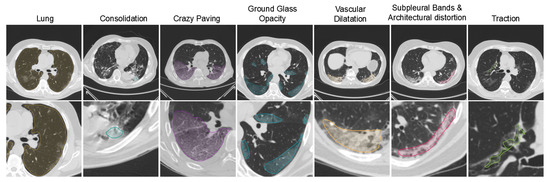

4.1. COVID-19 Quantification for VoI Detection

4.2. VoI Classification for COVID-19 Patient Risk Assessment